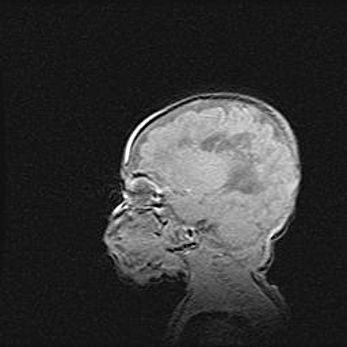

Мальформация Денди-Уокера. Киста задней черепной ямки.

Агенезия мозолистого тела.

Возраст: 2,5 месяца

Вес: 2420 г

Пол: женский

Окружность головы: 37 см

Срок гестации: 32 недели

Мальформация Денди—Уокера — редкий вид патологии ЦНС, представляющий собой врожденный порок развития каудального отдела ствола и червя мозжечка, ведущий к неполному раскрытию срединной (Мажанди) и латеральных (Лушка) апертур IV желудочка мозга. Для этогно синдрома характерна триада симптомов: гипотрофия червя мозжечка и/или полушарий мозжечка, кисты задней черепной ямки, гидроцефалия различной степени. В 70% случаев порок сочетается и с другими аномалиями головного мозга, в частности с агенезией мозолистого тела.